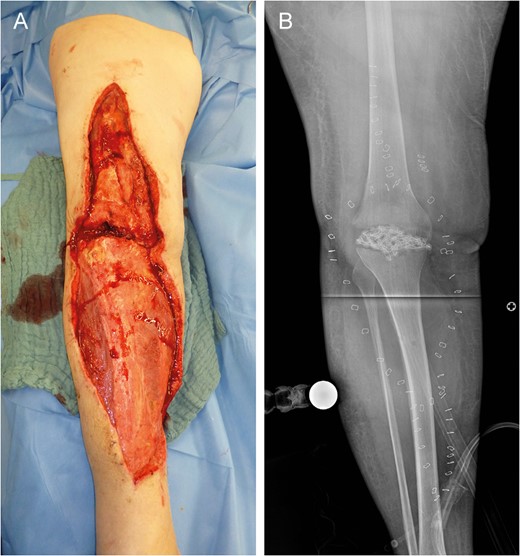

Eleven days after tissue coverage: suppurative, necrotic ulcers (arrows) on flap (A) and donor sites (B and C).